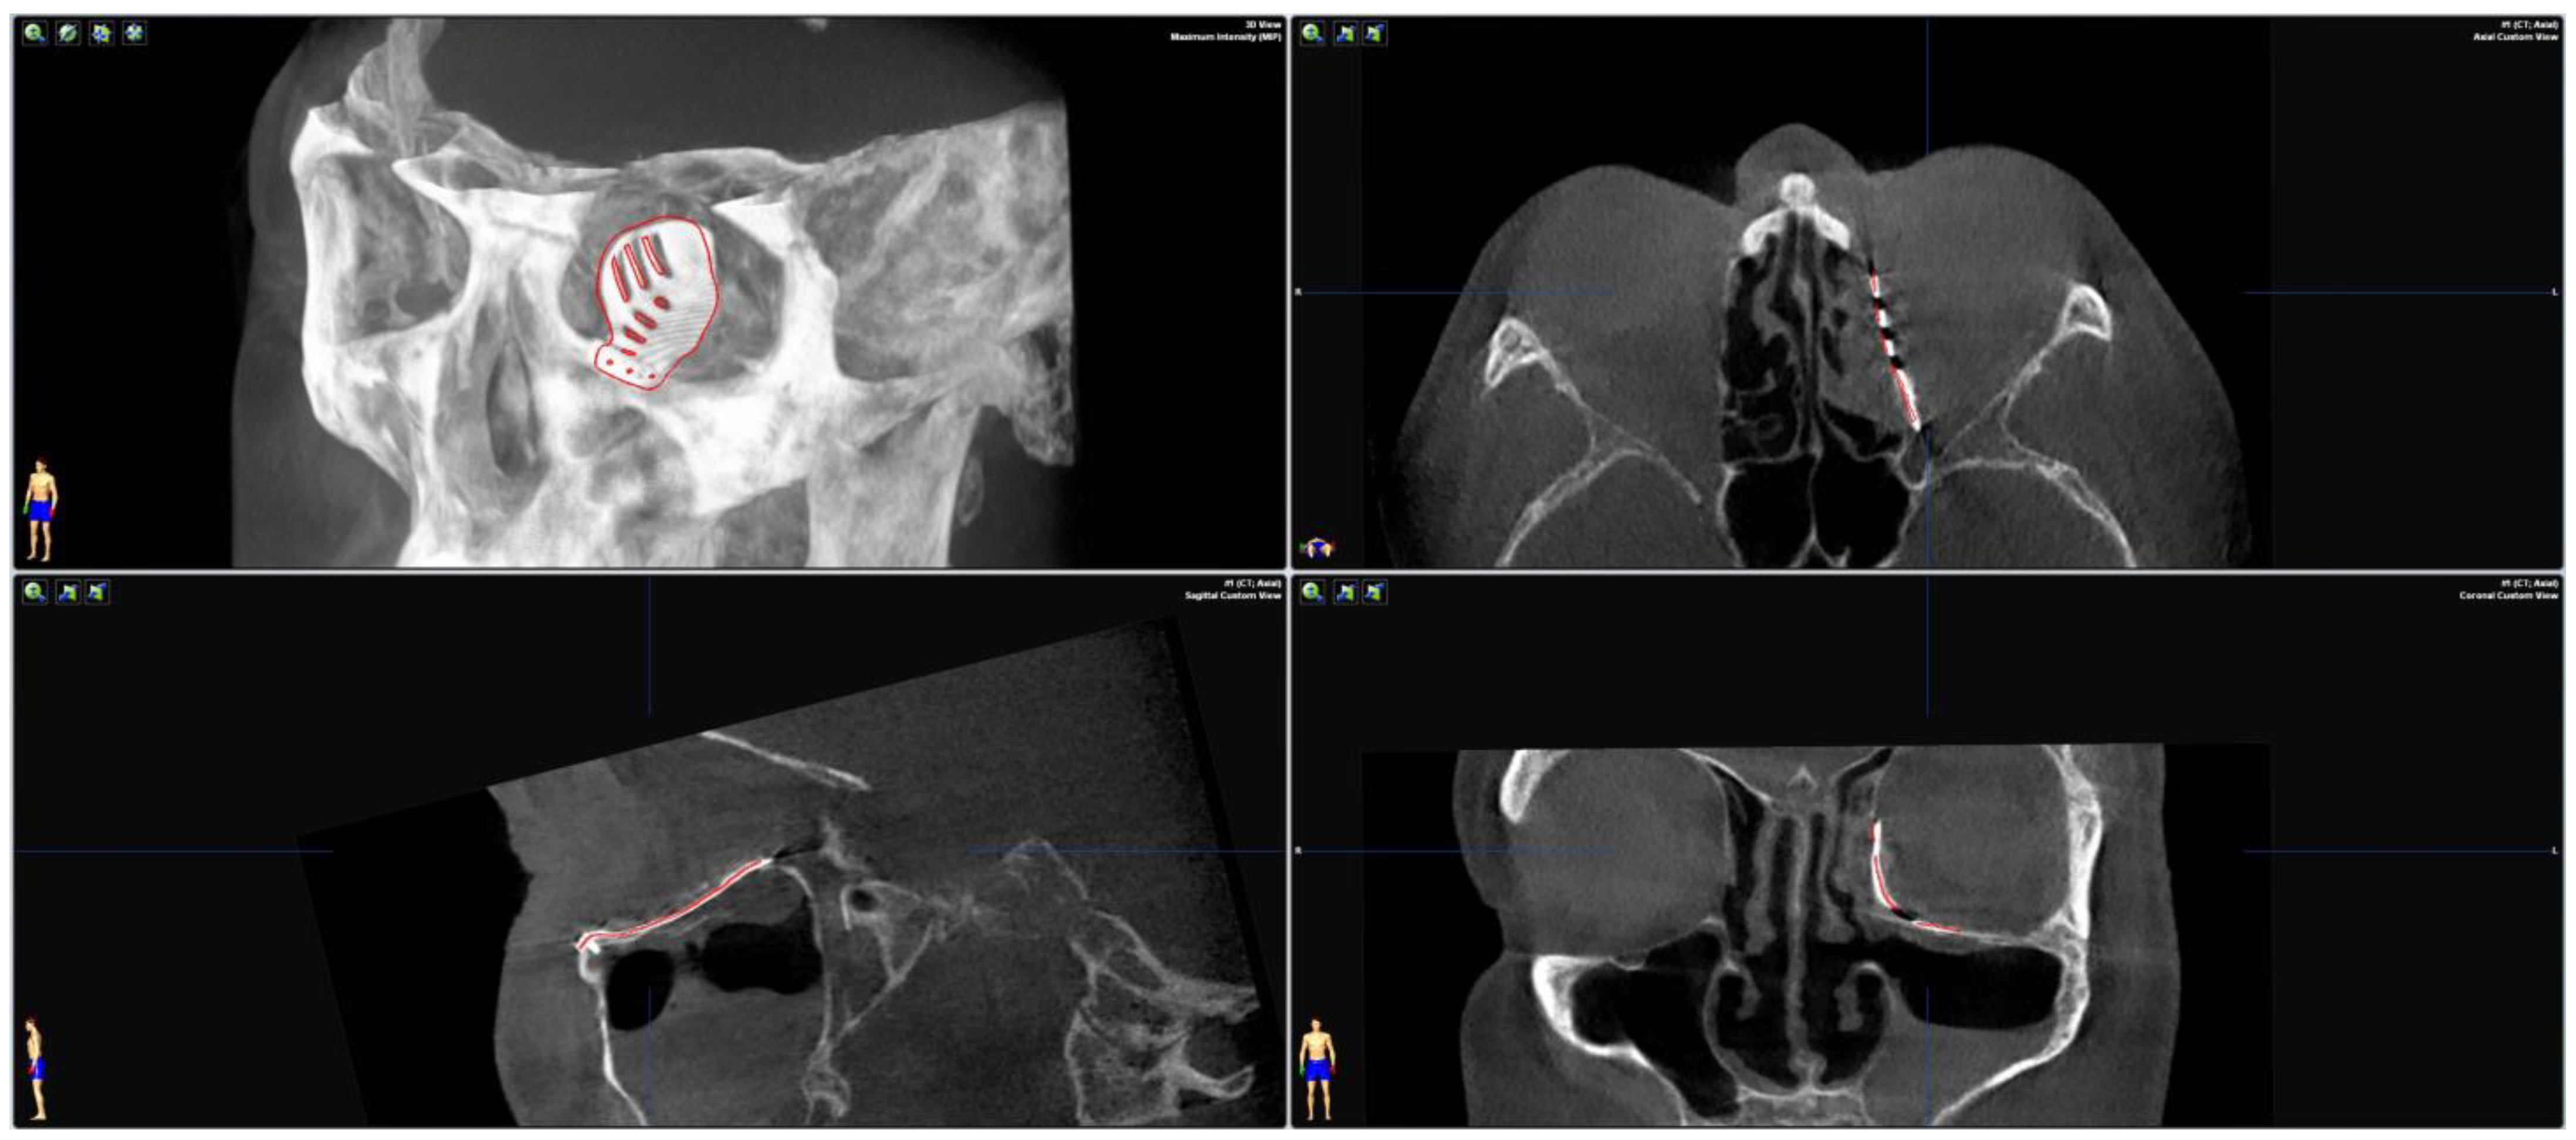

2.2. Surgery